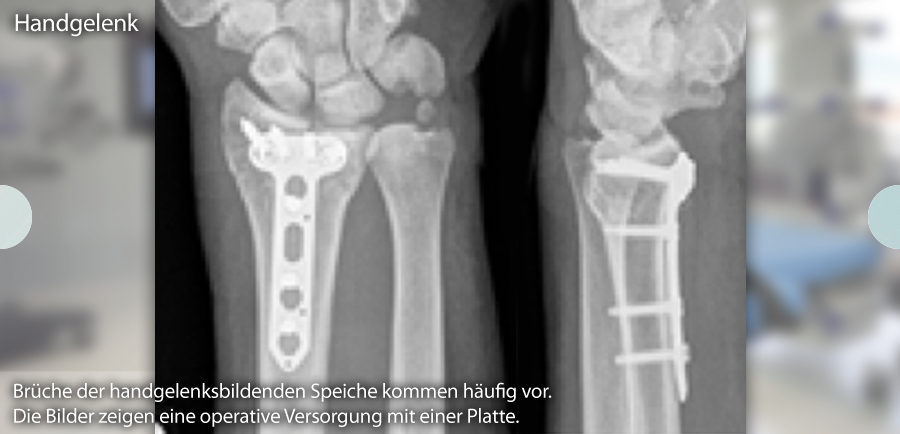

Zu den häufigsten Verletzungen großer Gelenke zählen Handgelenk, Schulter, Ellbogen, Sprunggelenk, Knie und Hüfte. Eine besondere Expertise ist für jedes Gelenk erforderlich, insbesondere bei seltenen Verletzungen, bei kindlichen Brüchen oder bei ausgeprägter Osteoporose.

Bei Klick auf die folgenden Bilder können Sie sich diese in vollständiger Größe anzeigen lassen: